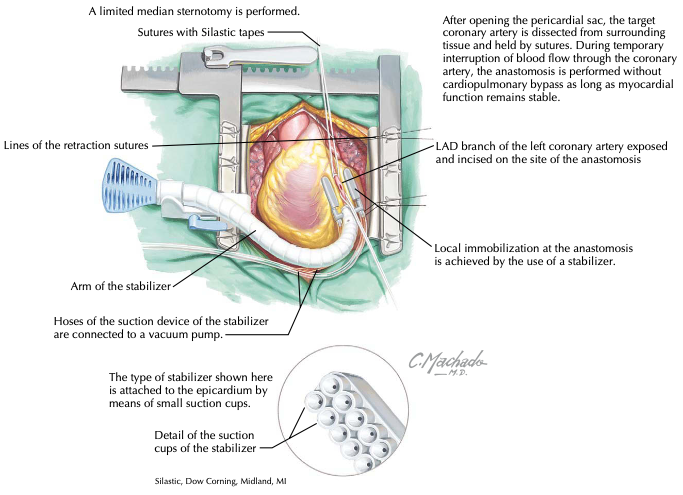

O emprego da artéria torácica interna esquerda ( AITE ) como enxerto para artéria interventricular anterior (AIA) é realizado por…

Historicamente, o desenvolvimento gradativo da cirurgia cardiovascular foi intimamente relacionado à cirurgia de revascularização do miocárdio (RM) no tratamento…